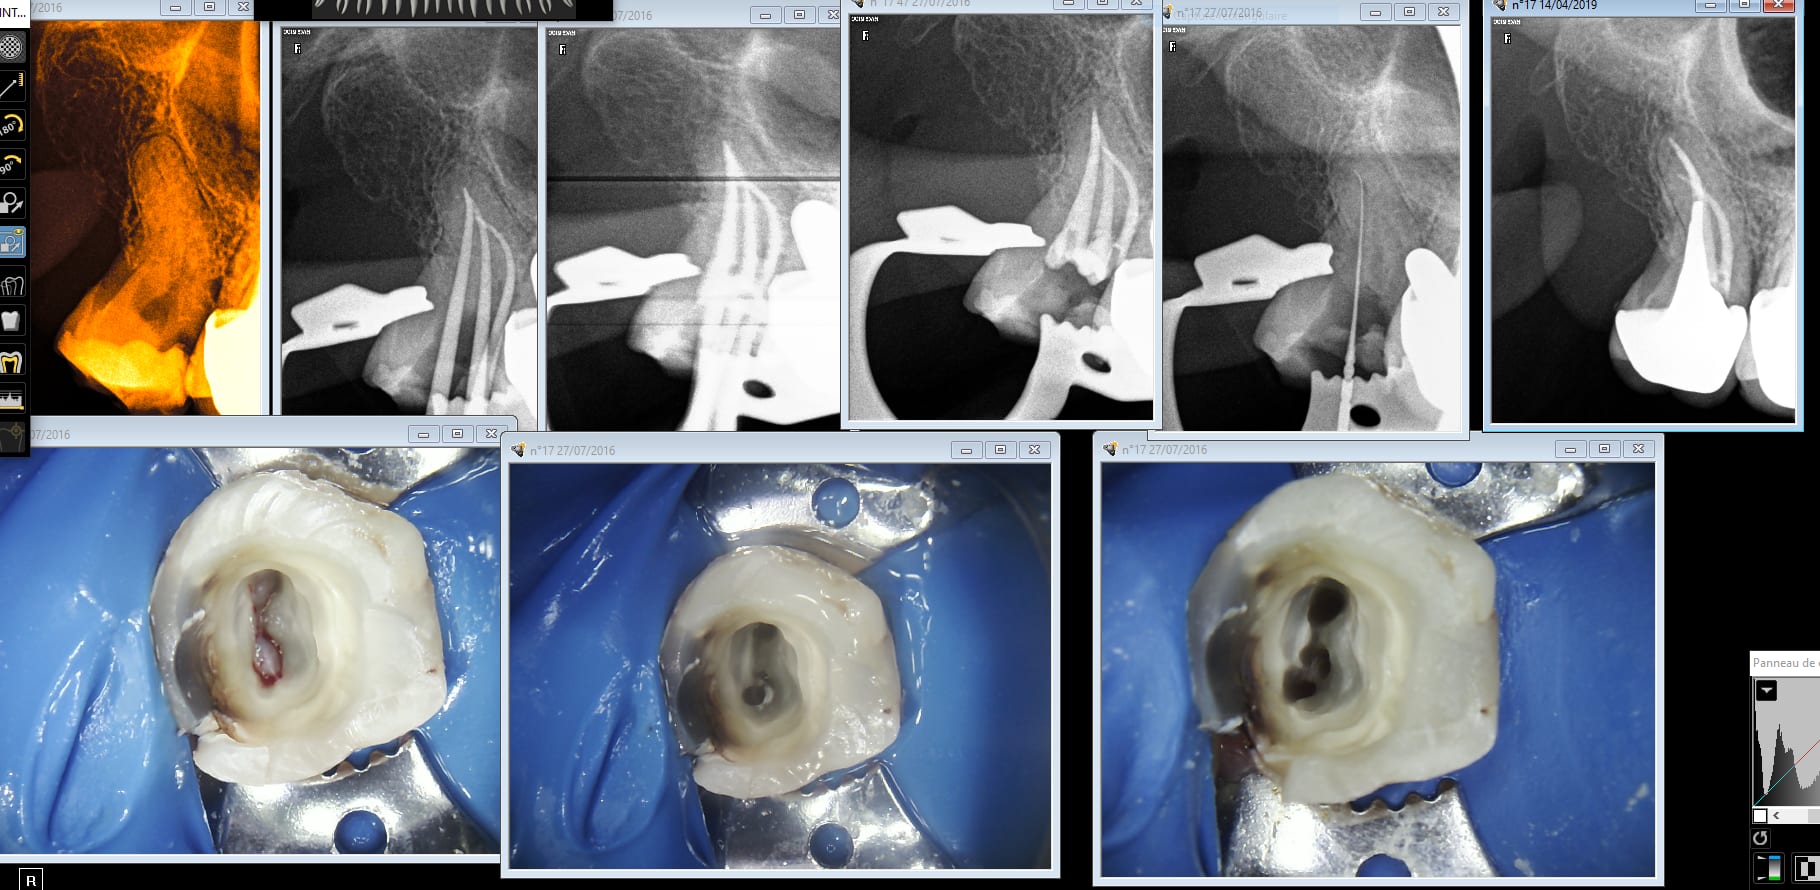

et ça ç est sympa comme nouveaux patients

mg 1349 mjgbf5 - Eugenol

Un peu comme ça ? Sinon tu demandes la couronne en meme temps comme ça il ne se pose pas la question de retailler derrière. Néanmoins je pense qu'en ouane shot tu vas avoir des soucis avec ton prothésiste local enlaye. -)))

Putain poser une ceramique pourrie labocast hors de prix sur une endo low cost tarif sécu sur ma femme j'abuse. Ta famille a bien de la chance de t'avoir. Pour info celle d'à coté c'est made in France on voit tout de suite la différence l'anatomie la fonction tout y est. . -)))

Aud 25 cour jrjwox - Eugenol

Endo aud 17 j8optr - Eugenol